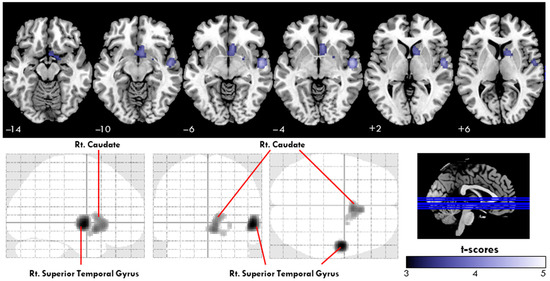

3.2. Voxel-Wise Comparisons of Cerebral Perfusion Imaging in Patients with SCD and HCs

Figure 2 illustrates the differences in cerebral perfusion between patients with SCD and HCs, with the cluster-level statistics for the significantly different regions summarized in Table 2. Regional cerebral blood flow (rCBF) in the right superior temporal gyrus (rSTG) was significantly lower in the SCD group compared to the healthy controls. Specifically, the mean uptake ratio in the rSTG was 0.864 ± 0.090 for the SCD group, compared to 1.030 ± 0.074 for the control group (p < 0.001, 95% confidence interval (CI): −0.1264 to −0.03918). Similarly, the mean uptake ratio in the right caudate was 0.783 ± 0.068 for the SCD group, compared to 1.030 ± 0.074 for the control group (p < 0.001, 95% CI: −0.1327 to −0.03058).

Figure 2. Regions showing significant differences in uptake ratio (UR) between patients with subjective cognitive decline (SCD) and healthy controls (HCs), as revealed by voxel-based analysis. The cold color map showed a significant reduction in URs in the right superior temporal gyrus and right caudate in patients with SCD. Glass-brain images showed the spatial distribution of UR reduction in patients with SCD (corrected p < 0.05). No area of increased UR was found in the SCD group compared to the HC group. (SCD, subjective cognitive decline; Rt, right).